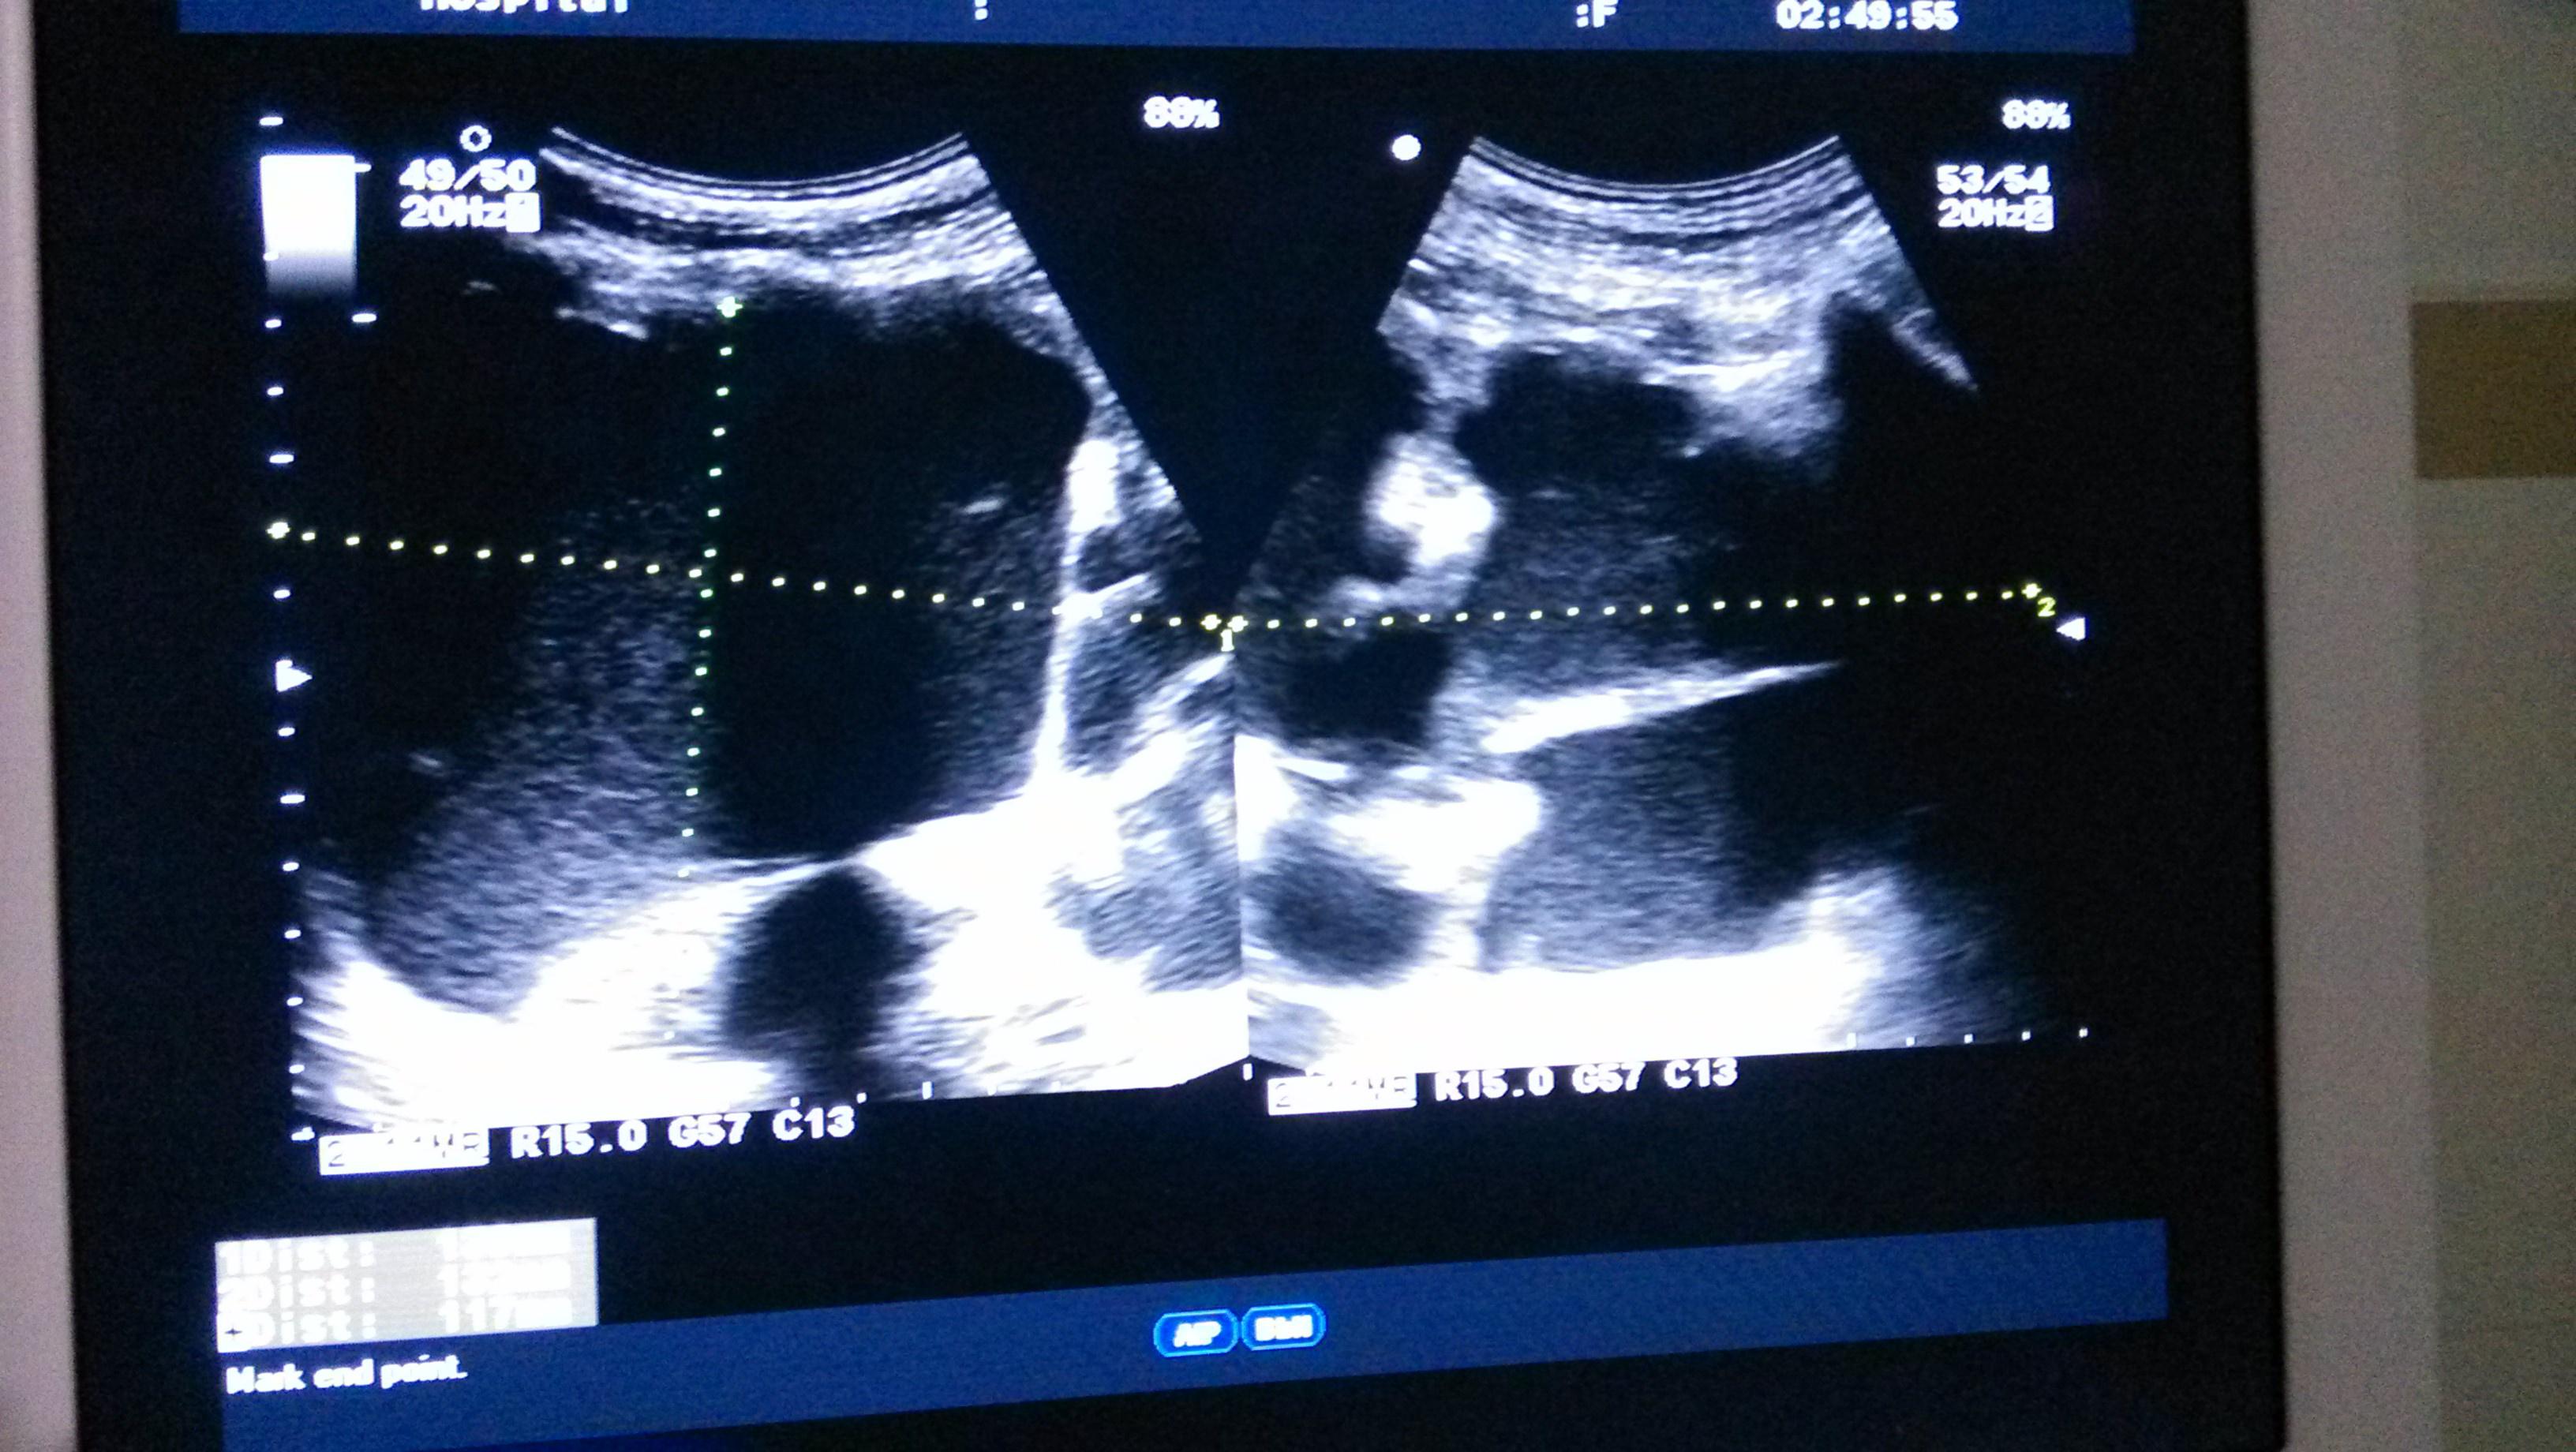

输尿管结石致右肾积水 - 超声医学讨论版 - 爱爱医医学论坛

图片尺寸720x576